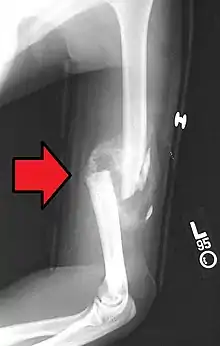

- Non-union: no progression of healing within six months of a fracture occurring. The fracture pieces remain separated and can be caused by infection and/or lack of blood supply (Ischaemia) to the bone.[9] There are two types of non-union, atrophic and hypertrophic. Hypertrophic involves the formation of excess callus leading to bone ends appearing sclerotic causing a radiological "Elephants Foot" appearance[6] due to excessive fracture ends mobility but adequate blood supply.[4] Atrophic non-union results in re-absorption and rounding of bone ends[6] due to inadequate blood supply and excessive mobility of the bone ends.[4]

- Mal-union: healing occurs but the healed bone has 'angular deformity, translation, or rotational alignment that requires surgical correction'. This is most common in long bones such as the femur.[10]